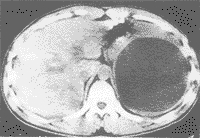

(1)真性囊肿:有表皮样囊肿、皮样囊肿、血管和淋巴管囊肿等,它与假性囊肿的区别在于囊内壁被覆扁平、立方或柱状上皮。其中表皮样囊肿多见于青年,常为单发性,最大直径可达31cm,囊内液体多达4000ml,色质浓稠,为淡红色或褐色,可有胆固醇结晶;病理形态可见,囊内壁衬以鳞状上皮,基底膜平整,无表皮钉突,无皮肤附属器。而表皮样囊肿来源不明,可能为胚胎期胃背侧系膜或中肾管的细胞误入脾内发育而成;其病理所见囊壁内衬鳞状上皮及附属器,为皮肤全层结构,可有神经组织及骨组织等,囊内可有白细胞、脂肪小体和胆固醇结晶。

(2)假性囊肿:较真性囊肿多见,约占非寄生虫囊肿的80%,囊肿多为单房性,可有外伤史,囊肿可以很大,囊壁无内皮细胞被覆。